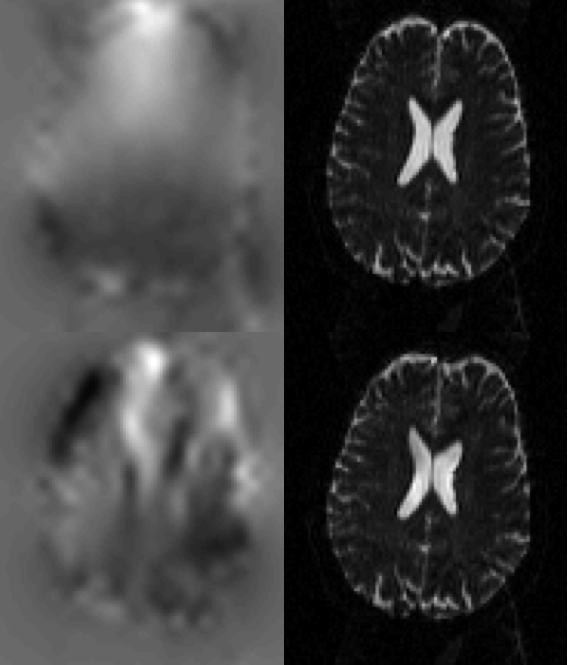

|

| In the top row is a pair of images with Ant->Post (left panel) and Post->Ant (middle panel) PE-encoding, and the resulting field estimated by TOPUP. In the second row we can see the same Ant->Post image (left panel), but now the subject has deliberately moved prior to the acquisition of the Post->Ant image. Despite that, thanks to TOPUP's internal movement model, the field has been accurately estimated. It can be seen in the lower right panel that there is very little difference to that in the upper right panel. |

| This figure shows the results from running TOPUP with (top row) and without (bottom row) the internal movement model. The left column shows the estimated field and the right column shows the corrected image. The pair that was used to estimate the field can be seen in the first two columns of the bottom row in the figure above. The image that was corrected is that from the middle column, bottom row in the figure above. It can be seen that without the movement model the field is very poorly estimated. Perhaps most worrying is that while the corrected image is "wrong" (compare the top and bottom row of the right column) it doesn't look "obviously wrong", and someone inspecting the corrected images as part of quality assurance is unlikely to detect any problem. |